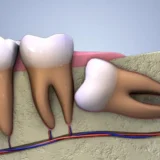

Để có hàm răng khỏe đẹp thì việc chăm sóc răng miệng là vô cùng cần thiết. Tuy nhiên, với một số trường hợp răng mọc lệch